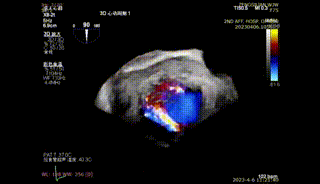

图1-4. 术前在交界、左室长轴切面及3D视角下可见大量二尖瓣反流,反流区宽,MultiVue下可见P2-P3脱垂

图11. 二夹解离后3D心房观